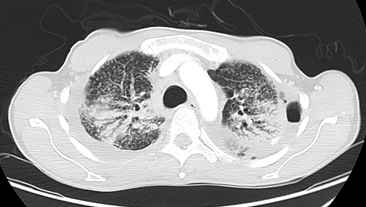

Realizamos TC con contraste yodado i.v. porque ofrece una resolución mucho mayor que la de la Rx de tórax, permitiéndonos valorar mejor la patología intersticial del paciente, así como confirmar que se trata de un neumotórax (pues veíamos una zona muy hipodensa). Además, esta técnica casi siempre se suele utilizar con contraste yodado, salvo en pacientes con riesgo de desarrollar una nefropatía aguda (si padece diabetes o enfermedad renal crónica, no siendo el caso de este paciente).